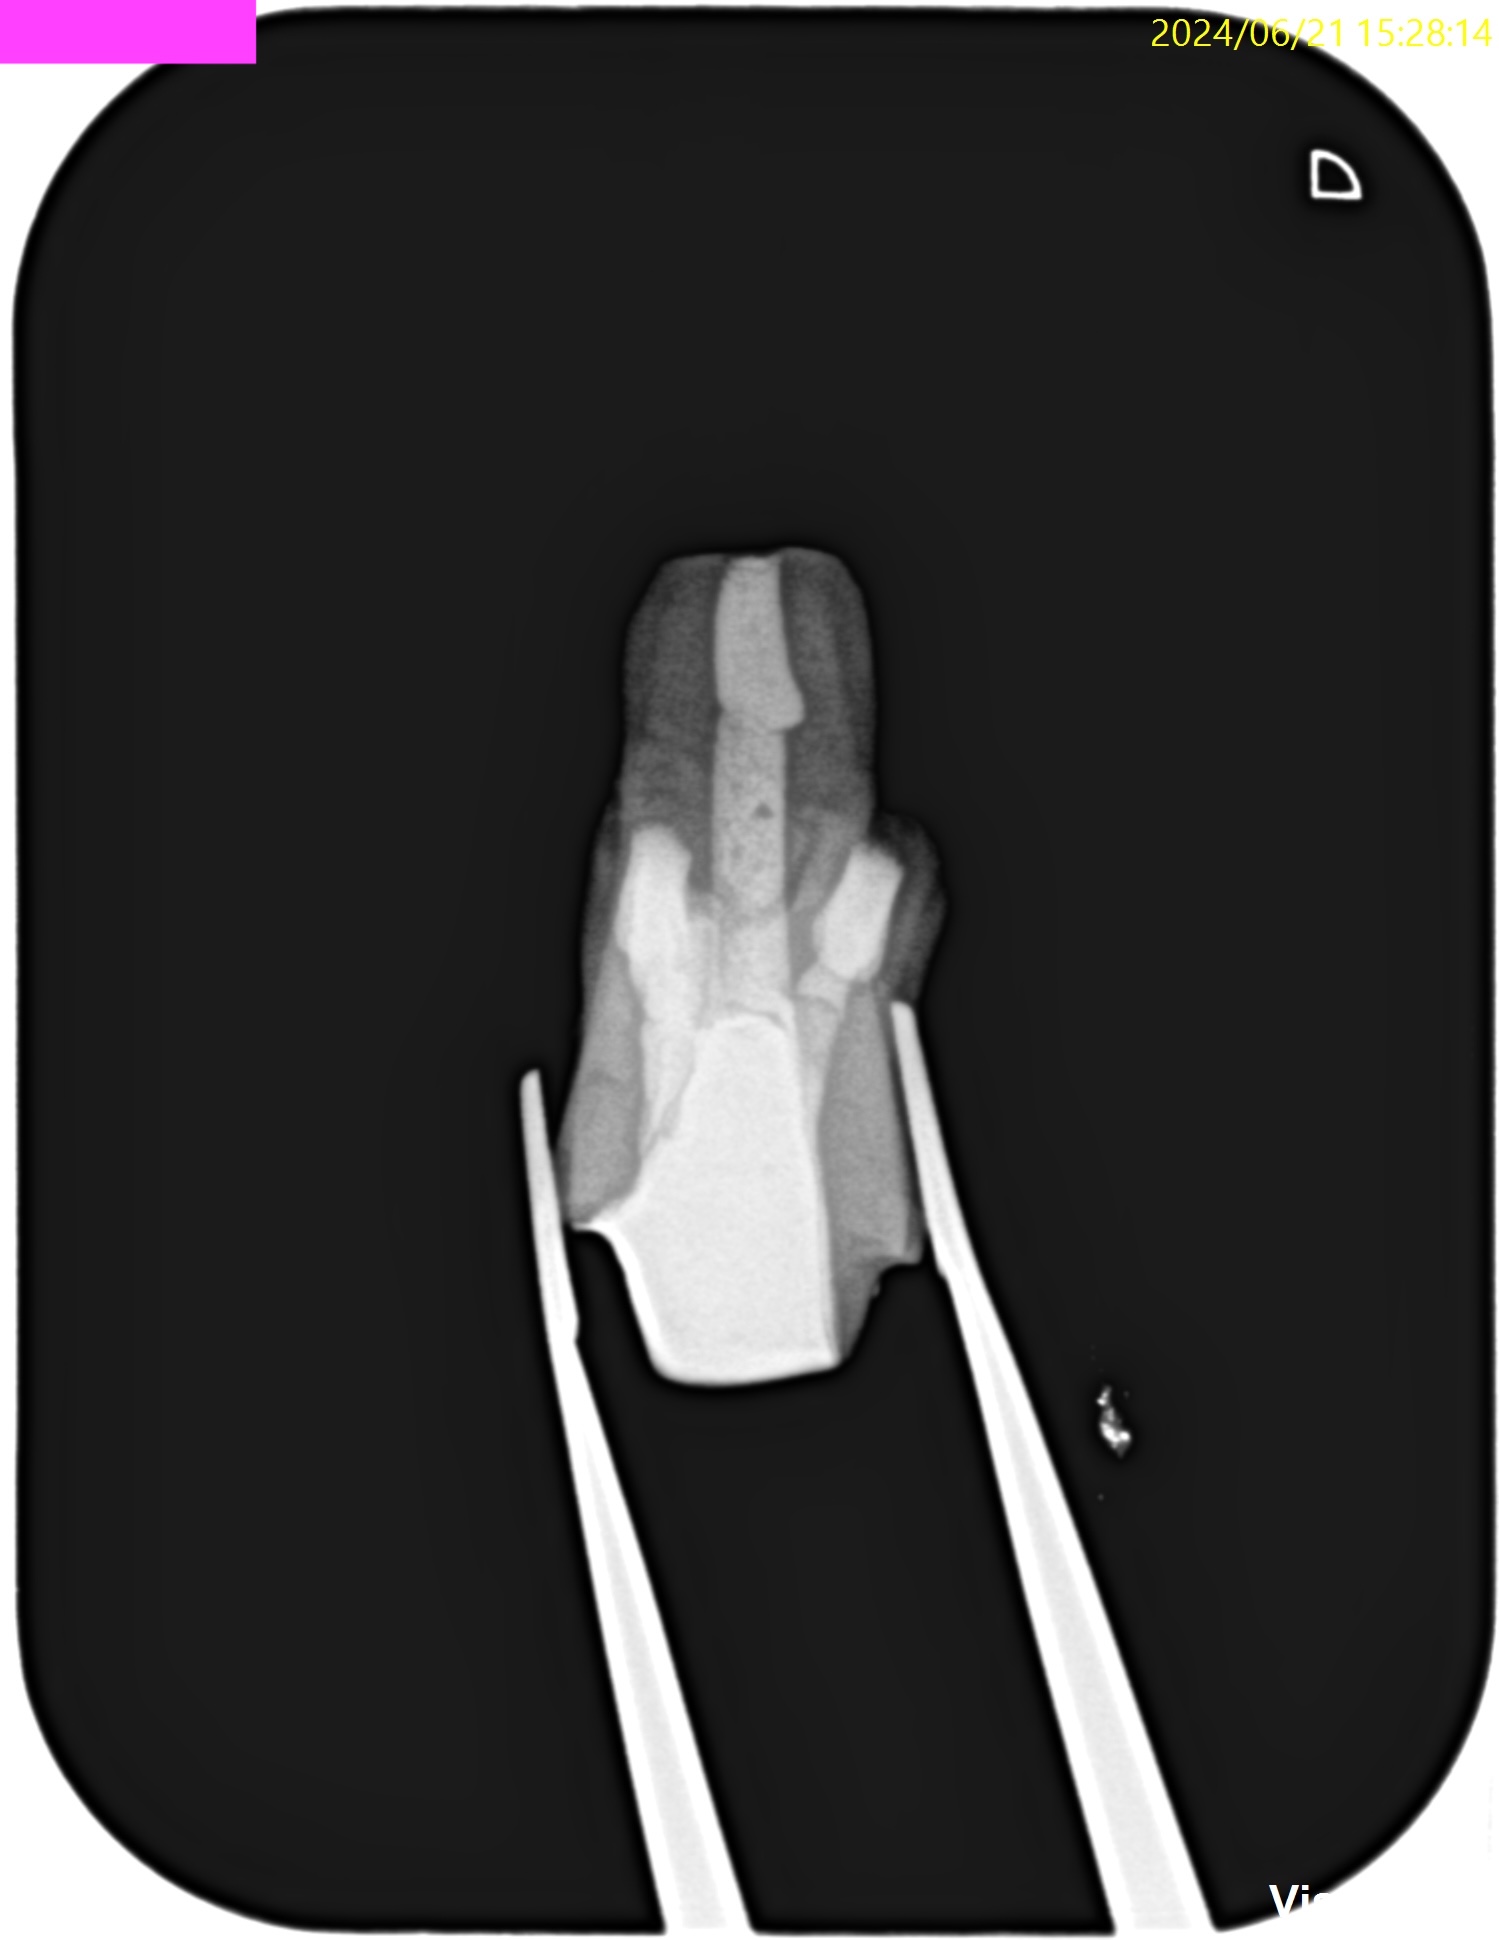

#14 Re-RCT(2023.6.20)

MB

DB

P

MB,DB,Pの3根全てに病変がある。

再根管治療を行うが、

DB以外はほぼ形成ができない状態であった。